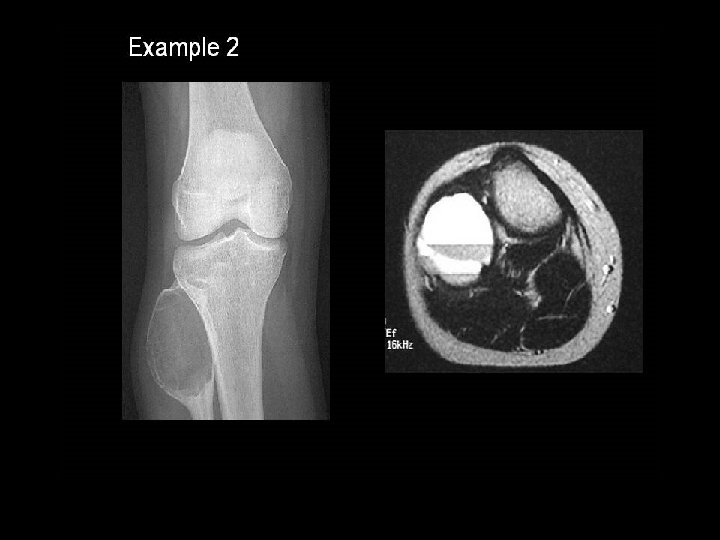

A 14 year old boy presents with pain and a mass above the knee. Take a look at the AP and lateral radiographs first.